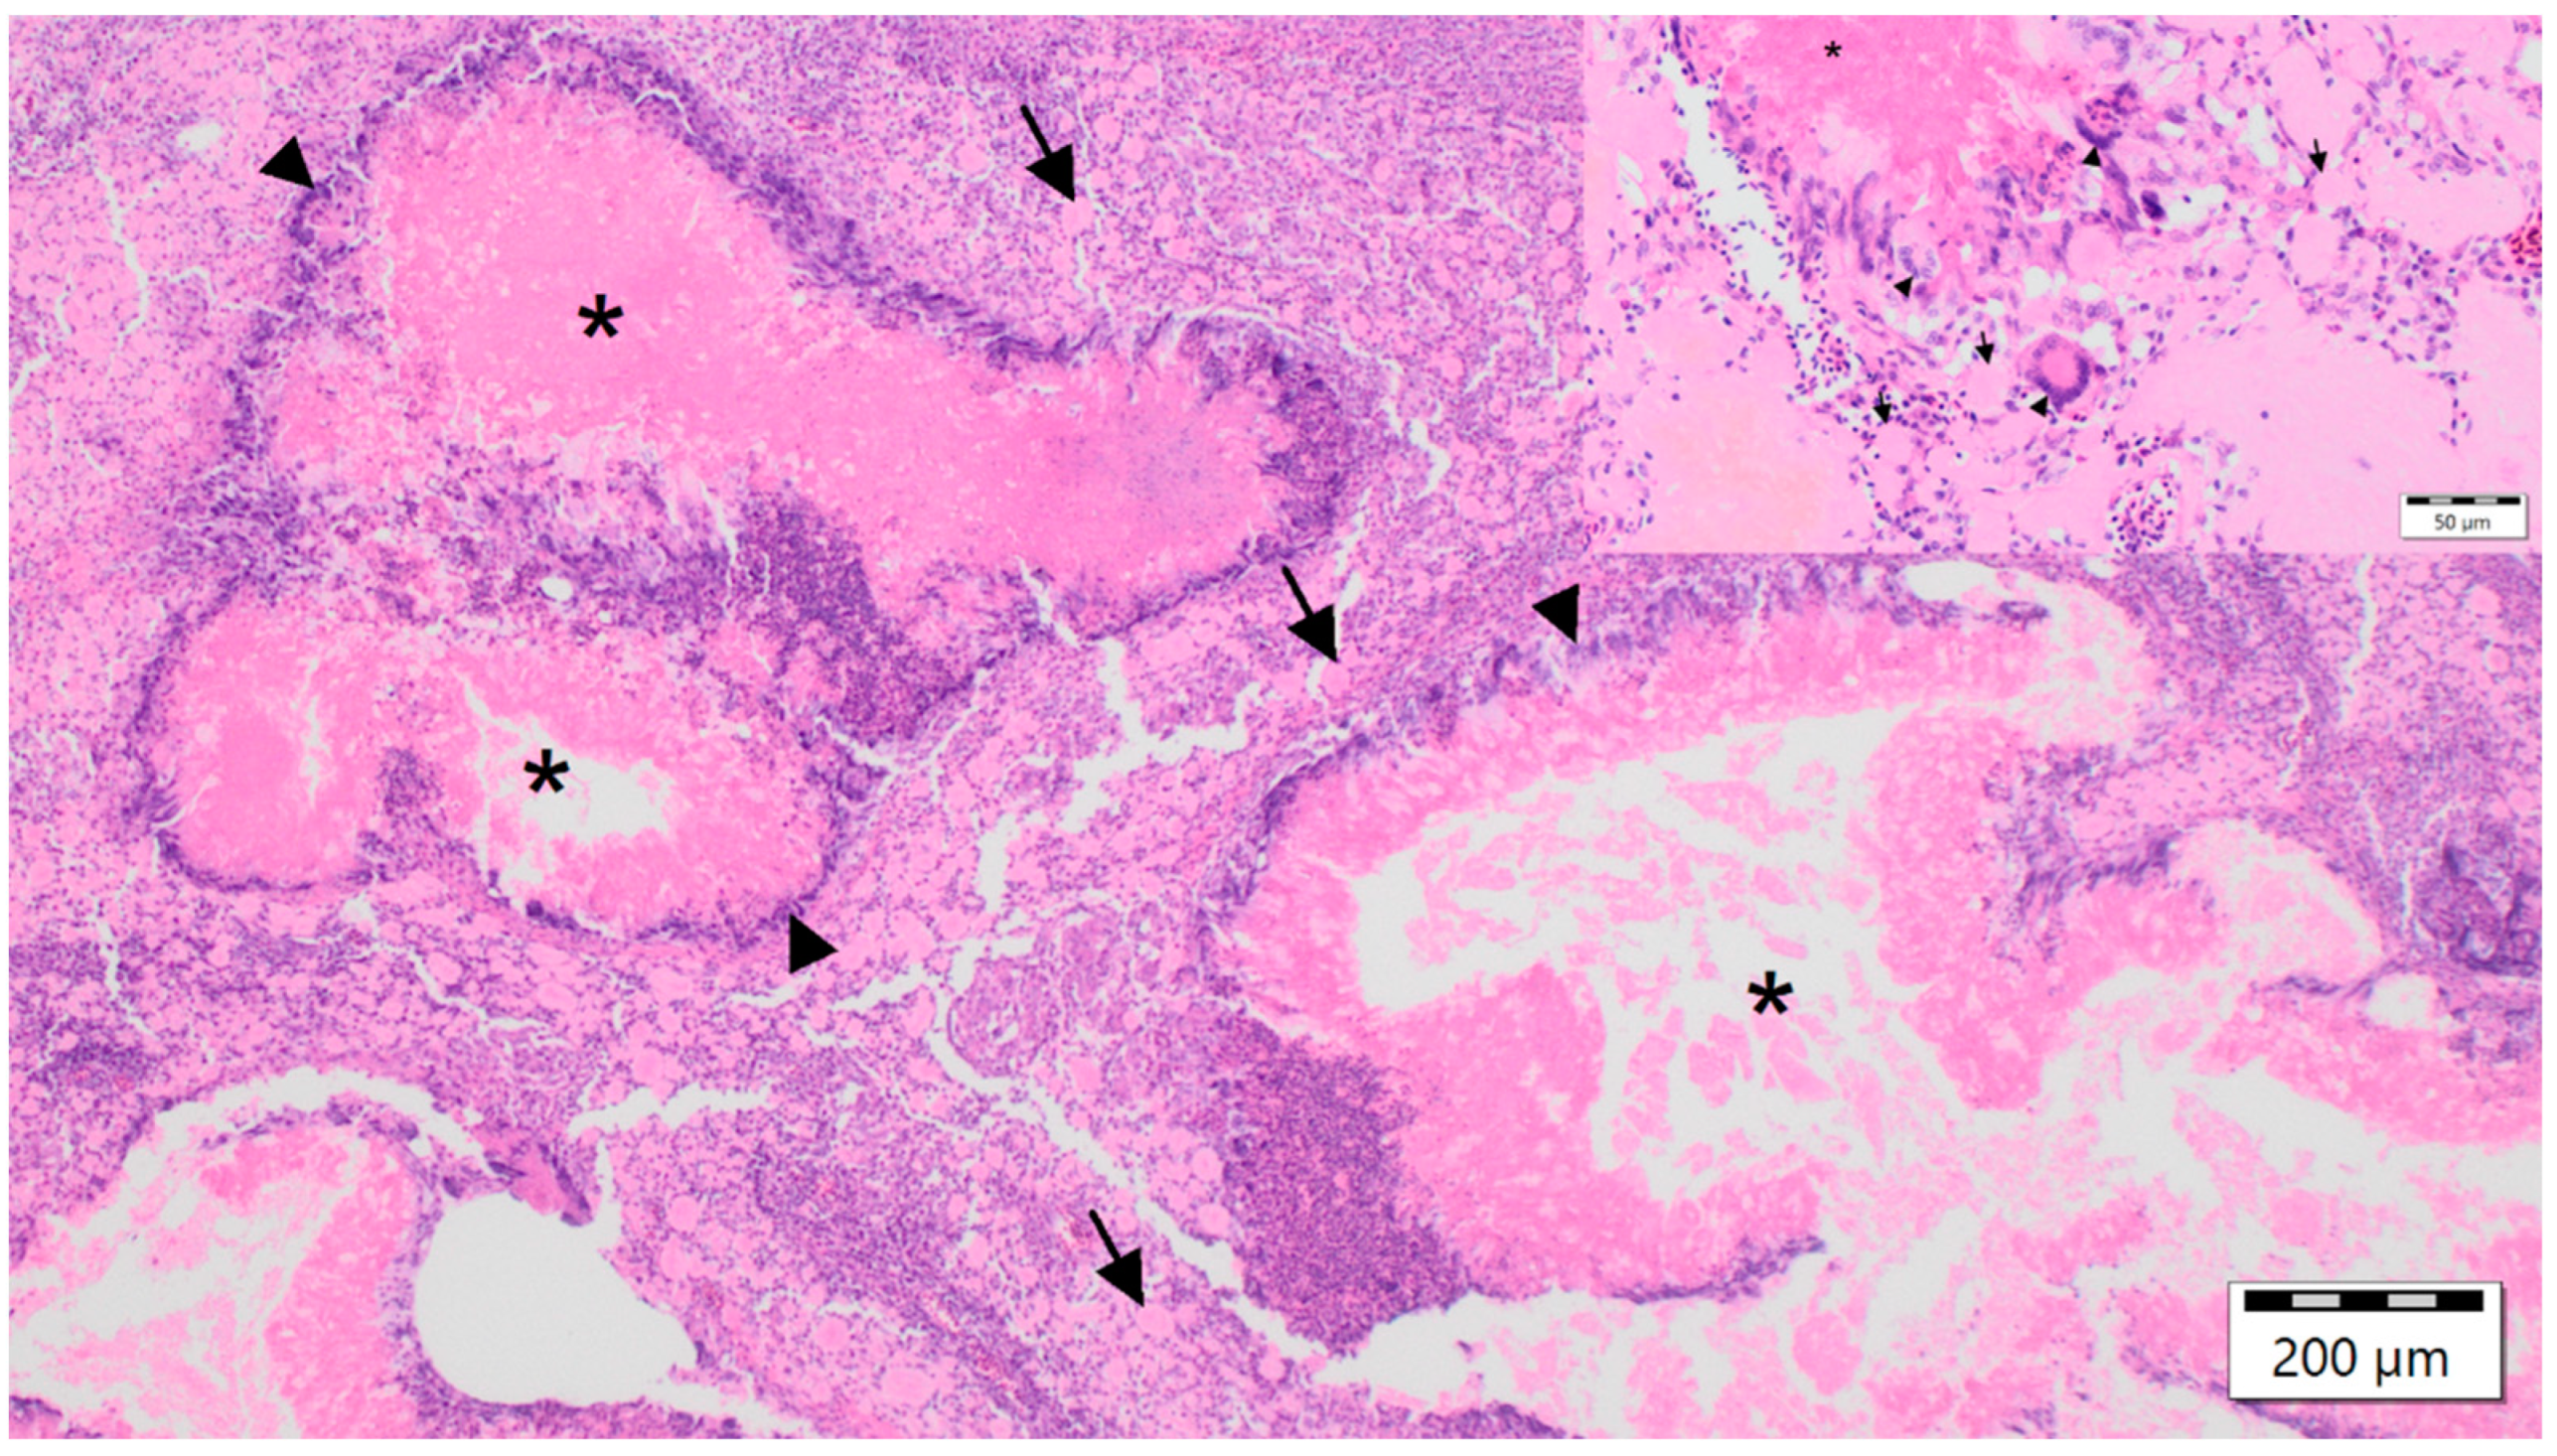

The nodules from birds with case nos. 1, 2, 4, 6 were characterized histopathologically by diffuse foamy and cholesterol-laden macrophages, multifocal fibrinous granulomas, central necrosis and fibrin, surrounded by multinucleated giant cells, histiocytes, lymphocytes and heterophils as well as various degrees of fibroplasia. Ziehl–Neelsen, Fite-Faraco, Von Kossa and Kongo red stains as well as PAS reaction were without additional findings, thus identifying these lesions as xanthogranulomatous inflammations [27,34] (Figure 3). In all six birds, large eosinophilic intranuclear inclusion bodies were documented in the epithelial cells of the collecting ducts of the kidney (Figure 4), regardless of the diagnosis of xanthogranulomas, which were present in four birds only. Additional findings in birds with xanthogranulomas (case nos. 1, 2, 4, 6) were splenic and renal haemosiderin in case no. 1, and subacute fibrinous conjunctivitis with isolation of Pseudomonas aeruginosa in case no. 6 (Table 1). The main histopathological findings in both birds without xanthogranulomas (case nos. 3, 5), in addition to viral nephritis, in case no. 3, comprised disseminated intravasal coagulation, necrotizing splenohepatitis with amphophilic intranuclear inclusion bodies inside reticular cells and hepatocytes, lymphocytic depletion of the lymph follicles of the spleen, acute catarrhal duodenitis, subacute ulcerative proventriculitis and subacute fibrinous fungal pneumonia, and in case no. 5, hepatic steatosis (Table 1).

Figure 3. Micrograph of a subcutaneous fascial nodular mass from a Red-crowned Parakeet (Cyanoramphus novaezelandiae) labelled as case no. 1, characterized by diffuse foamy and cholesterol-laden macrophages (black arrows), multifocal fibrinous granulomas with central necrosis and fibrin (black asterisk), surrounded by multinucleated giant cells (black arrowheads), histiocytes, lymphocytes and heterophils. Haematoxylin and eosin staining, 100× magnification and inlay 400× magnification.